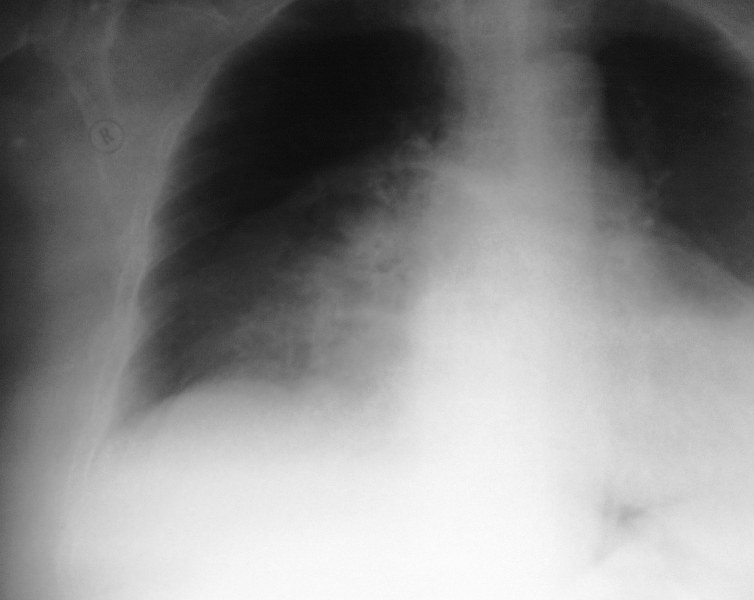

Рентгенография ОГК. Тучная пациентка с одышкой.

Справа в прикорневой зоне,на фоне инфильтрации л.ткани,очаг расспада?Корни расширены на фоне увеличеного сердца.Не плохо бы посмотреть и боковой.Но,наверное у Марио на КТ был уже ответ.Так что же было у этой пациентки?Абсцедирование?Но может быть и петля кишечника?

правосторонний пневмоторакс (справа легочный рисунок не прослеживается; коллабированное легкое) в области шеи толи артефакт то ли кальцинированный л/у но больше смущает объёмное образование больше справа в грудной клетке с горизонтальным уровнем жидкости; дала бы барий чтоб отдифференцировать(грудной желудок или дивертикул пищевода)